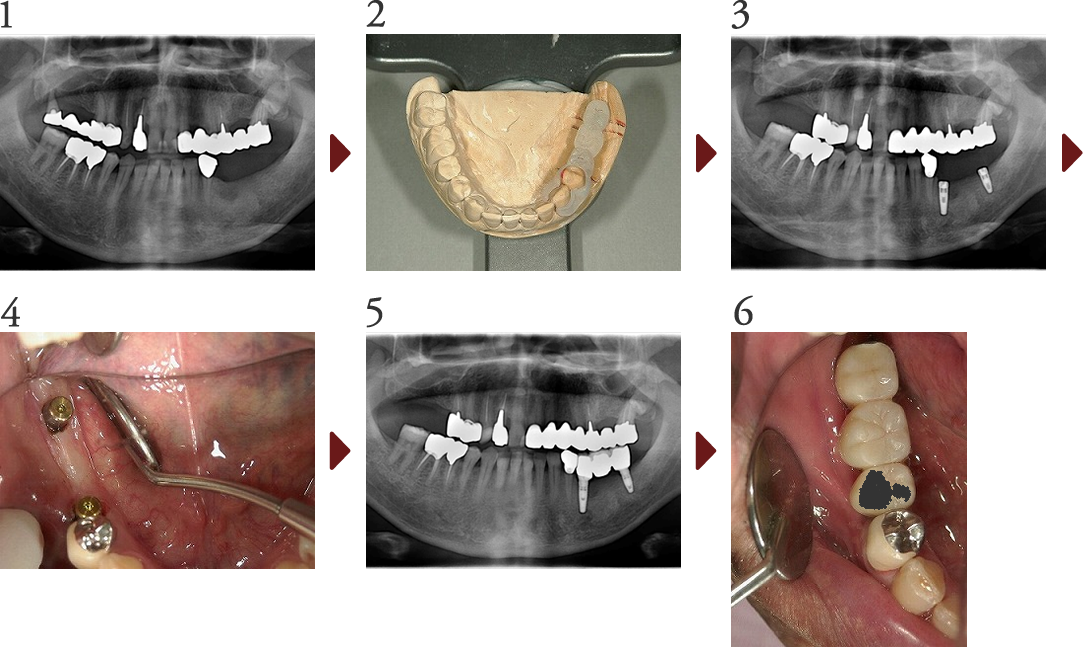

Case.2

前歯審美修復(ラミネートべニア修復 他)

患者さんは上顎前歯の歯並びの不揃い、変色、パッチワーク修復物による審美的なコンプレックスの改善を目的に、オールセラミックスによる審美修復を行う事となりました。

このように、未修復の天然歯と補綴された修復歯が混在するケースでは、歯全体の色調の調和がとれていないとバランスが悪くなり審美的とは言えなくなる為困難を要します。

今回は、オフィスホワイトニング、ラミネートべニア修復、オールセラミックスクラウン修復にて4前歯を修復しました。

また、上顎前歯未修復歯と下顎前歯との色調を調和させるため、クリスタルアイという機器によるデジタルシェードテイキング(機械的な測色)を行い、可及的に色調の調和が取れるよう治療を進めました。最終的には全体的に調和を保った修復治療になったのではないかと考えます。

(技工担当:北見市デンタルプランニング 工藤 利一氏)